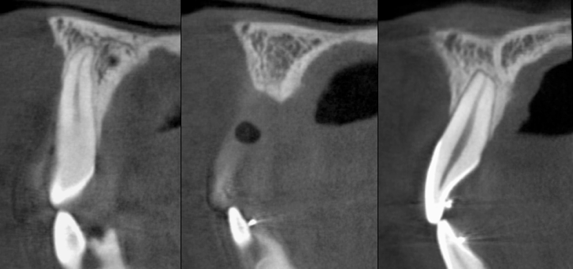

The patient had a congenitally missing upper right lateral incisor. Orthodontic treatment was performed to create the necessary space for a dental implant. Unfortunately, the implant failed, and so did several subsequent attempts to bone graft. These failures resulted in a visible smile deformity, that got worse after each failed procedure.

After the 3rd bone graft failed, the patient sought second opinions. She was a college sophomore at the time. Using a combination of interdisciplinary therapies, including S.M.A.R.T. minimally invasive bone grafting, Dr. Ernesto Lee was able to tridimensionally reconstruct this severe defect and place implants to restore the patient’s smile. The S.M.A.R.T. bone graft was also extended to treat adjacent teeth with thin/dehisced bone.